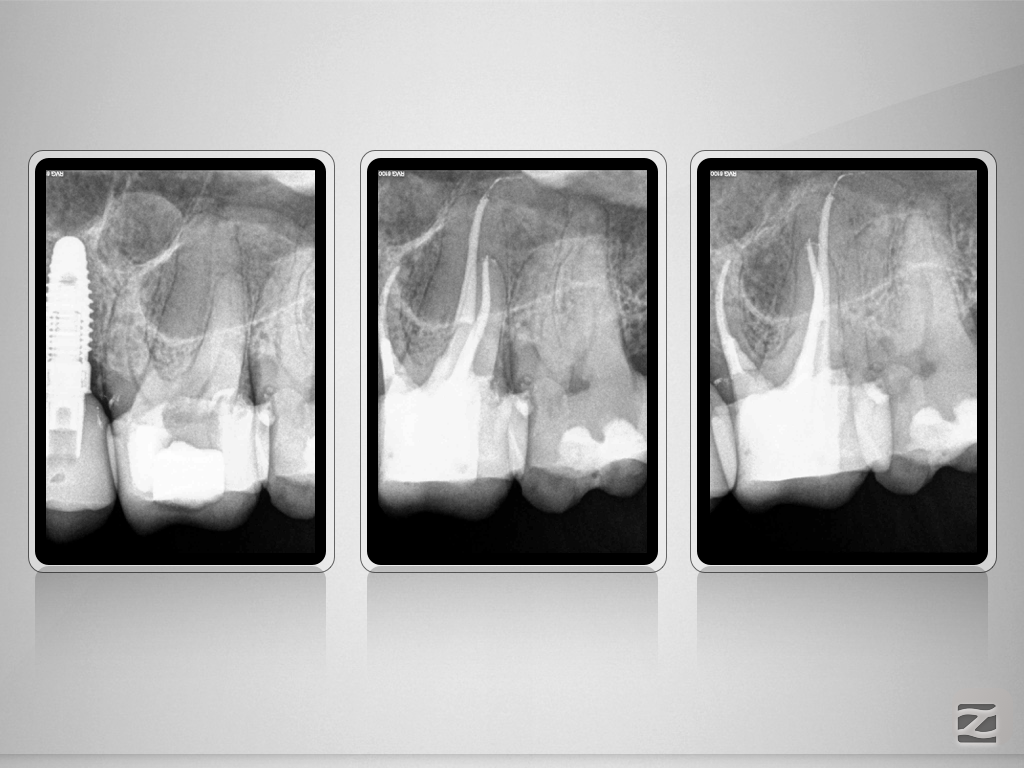

26D.006

Das Mikroskop-Bias